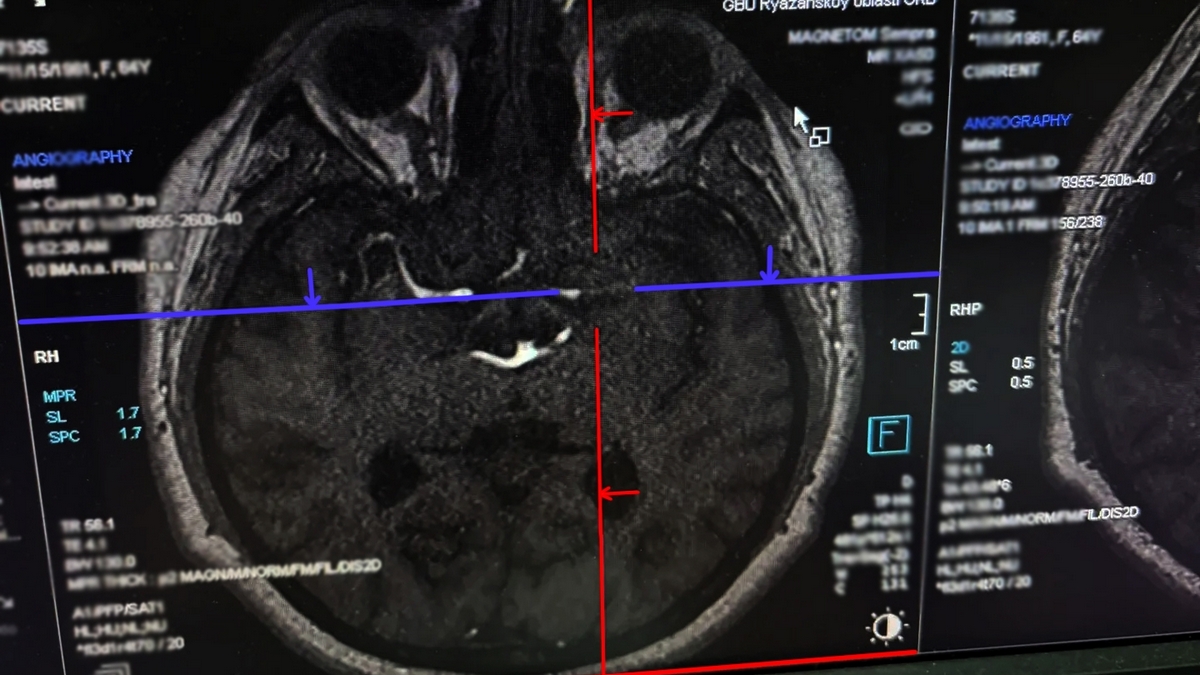

Курение вейпов привело к инсульту у 24-летнего парня: чудо-спасение врачей Рязанской больницы

По прибытии в больницу врачи оперативно начали проведение тромболитической терапии, которая помогла восстановить кровоток мозга. Благодаря своевременно оказанной помощи пациент быстро восстановился и снова начал ходить самостоятельно. После лечения мужчина был отправлен домой для дальнейшего амбулаторного наблюдения.

Источник фото: министерство здравоохранения Рязанской области